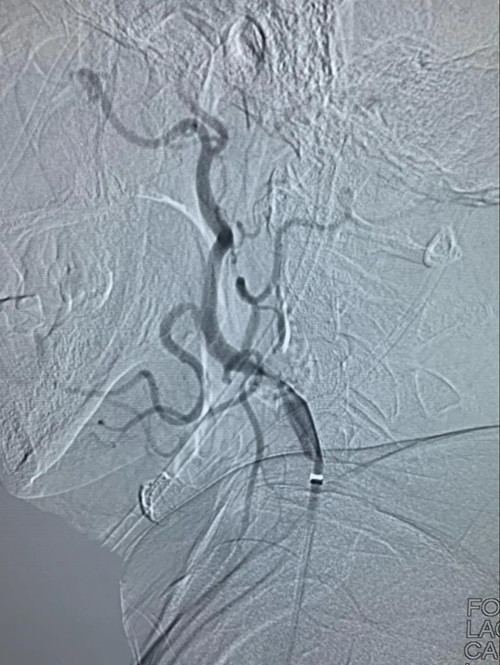

静脉溶栓治疗效果不明显,医生紧急启动介入治疗,为抢救患者生命争分夺秒。介入中心主任李光雷及副主任王振兴为患者急诊行血管造影检查,结果显示右颈内动脉起始段严重钙化斑块并闭塞。

右颈内动脉起始段严重钙化斑块并闭塞

两位主任根据以往经验,考虑患者发病机制为右颈内起始部重度狭窄基础上急性闭塞,同时伴有血栓脱落造成动脉-动脉的右大脑中动脉闭塞,立即给予介入取栓治疗。